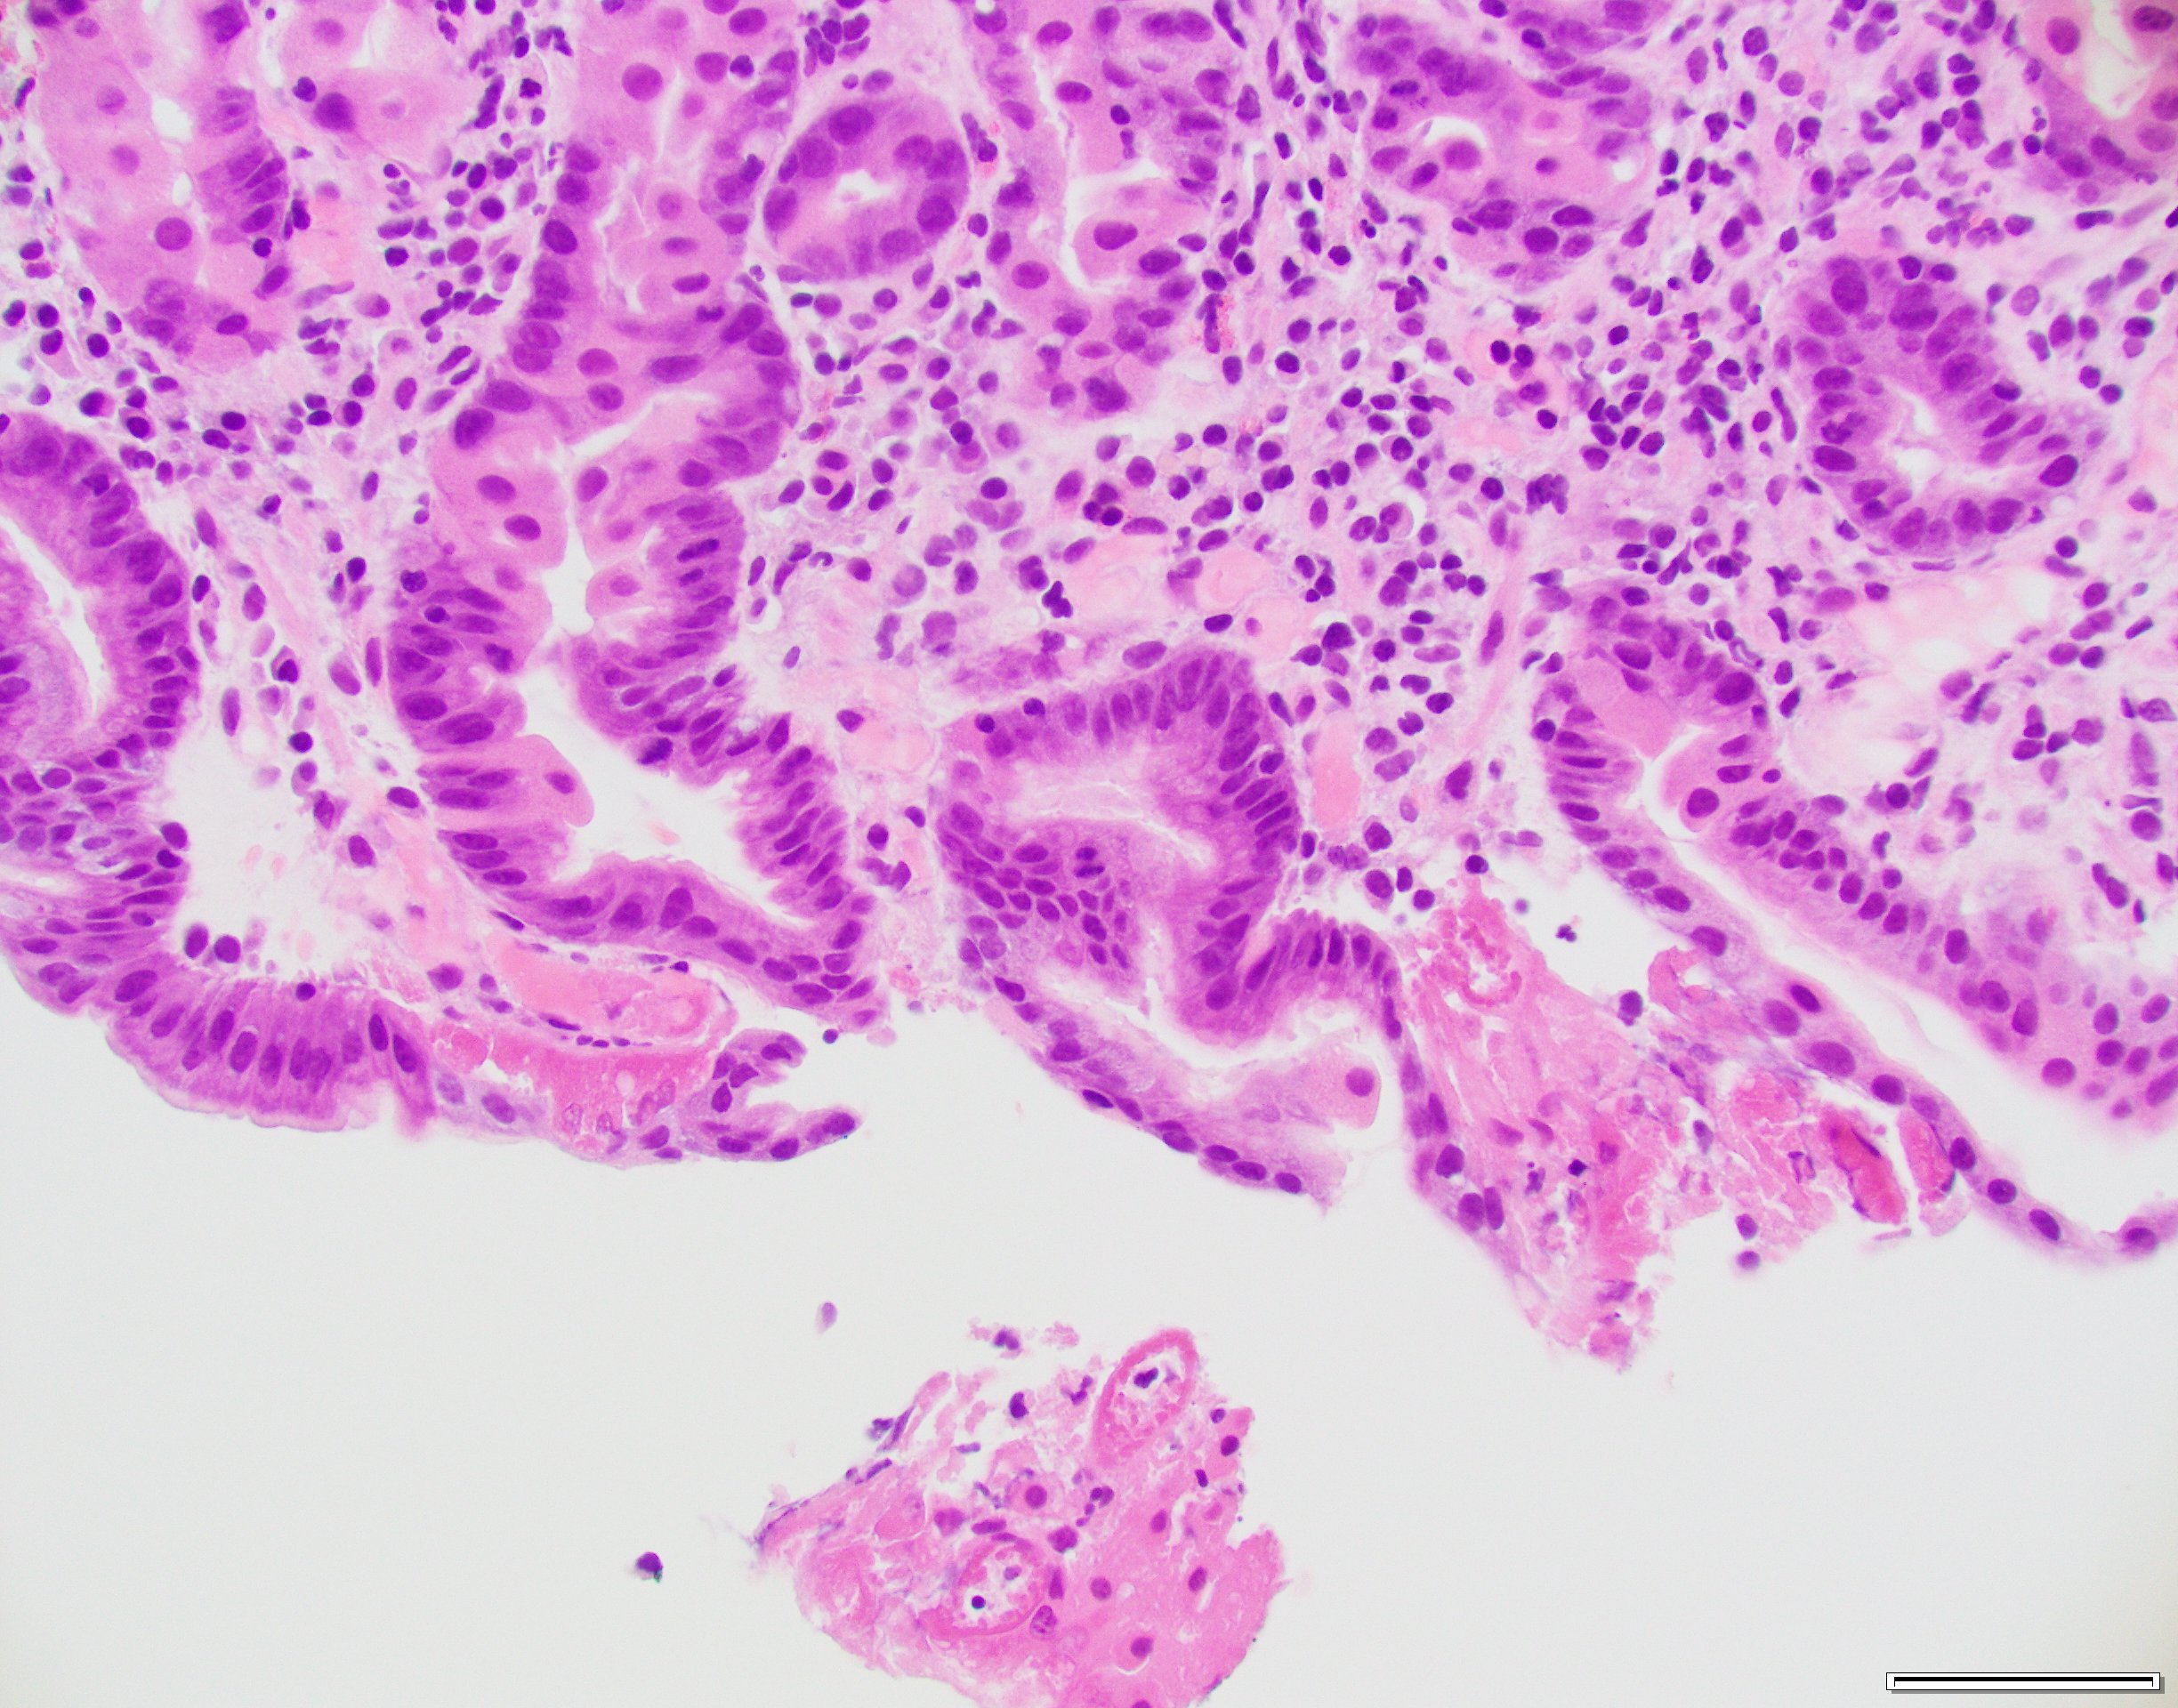

Case History

Gastric biopsy in an 80-year-old female.

What is the best diagnosis?

- H. pylori gastritis

- Autoimmune gastritis

- Iron-pill gastritis

- Doxycycline-associated gastritis

Answer: This biopsy shows eosinophilic necrosis of the superficial capillaries and capillary microthrombi. These histologic features are characteristically described with doxycycline-related gastric mucosal injury. H. pylori immunostain was negative.

Case contributed by: Deepti Dhall, M.D., Professor & Associate Director, Anatomic Pathology, GI Section Head